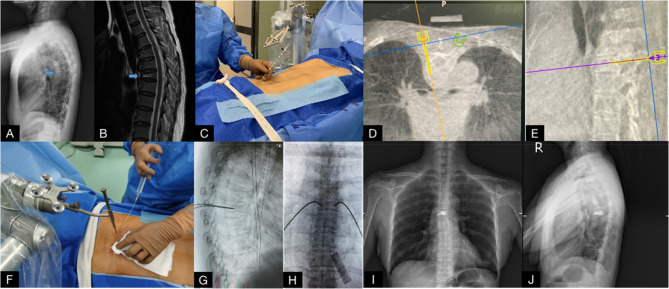

Methods: A retrospective analysis was performed on 62 patients with OVCF of the middle and upper thoracic vertebrae (T1-T8) who underwent PVP surgery in Shenzhen Traditional Chinese Medicine Hospital from January 2017 to January 2023. Of them, 30 and 32 patients underwent TiRobot-assisted PVP surgery (robot group) and conventional C-arm-assisted PVP surgery (conventional group), respectively. VAS and ODI scores and the anterior height and local kyphotic angle of the fractured vertebra were compared before surgery and 3 days, 1 month, and 1 year after surgery. Simultaneously, the operation time, intraoperative blood loss, puncture frequency, fluoroscopy frequency, hospital stay, surgeon radiation exposure, patient radiation exposure, bone cement leakage, cement distribution, and complication were compared between the two groups.

Results: VAS score and ODI score at 3 days, 1 month, and 1 year after surgery were significantly improved in both groups compared with those before surgery (p < 0.05). The VAS score of the robot group was lower than that of the conventional group 3 days after surgery (p < 0.05), with no significant difference observed before and after surgery (p > 0.05). No significant difference was observed in anterior height and local kyphotic angle of fractured vertebra between the two groups before and after the surgery (p > 0.05). The operation time, intraoperative blood loss, puncture frequency, fluoroscopy frequency, hospital stay, surgeon radiation exposure, patient radiation exposure, bone cement leakage, and cement distribution of the robot group were all better than those of the conventional group (p < 0.05). Simultaneously, the incidence of complications in the robot group was 3.33% (1/30) lower than that of the conventional group (15.62%) (5/32) (p < 0.05).

Conclusions: Compared with traditional PVP surgery, the use of TiRobot-assisted PVP in the treatment of middle and upper thoracic OVCF has the advantages of accuracy, safety, and low-radiation exposure, which can further improve surgical safety, reduce bone cement leakage, and achieve satisfactory clinical efficacy.